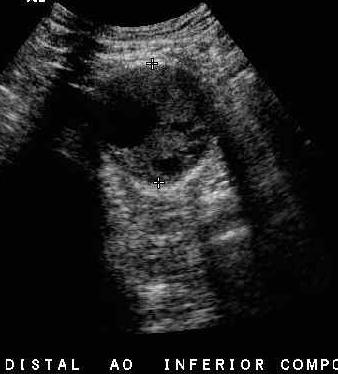

60yo male with vague abdominal pain x4mos

What is this pathology?